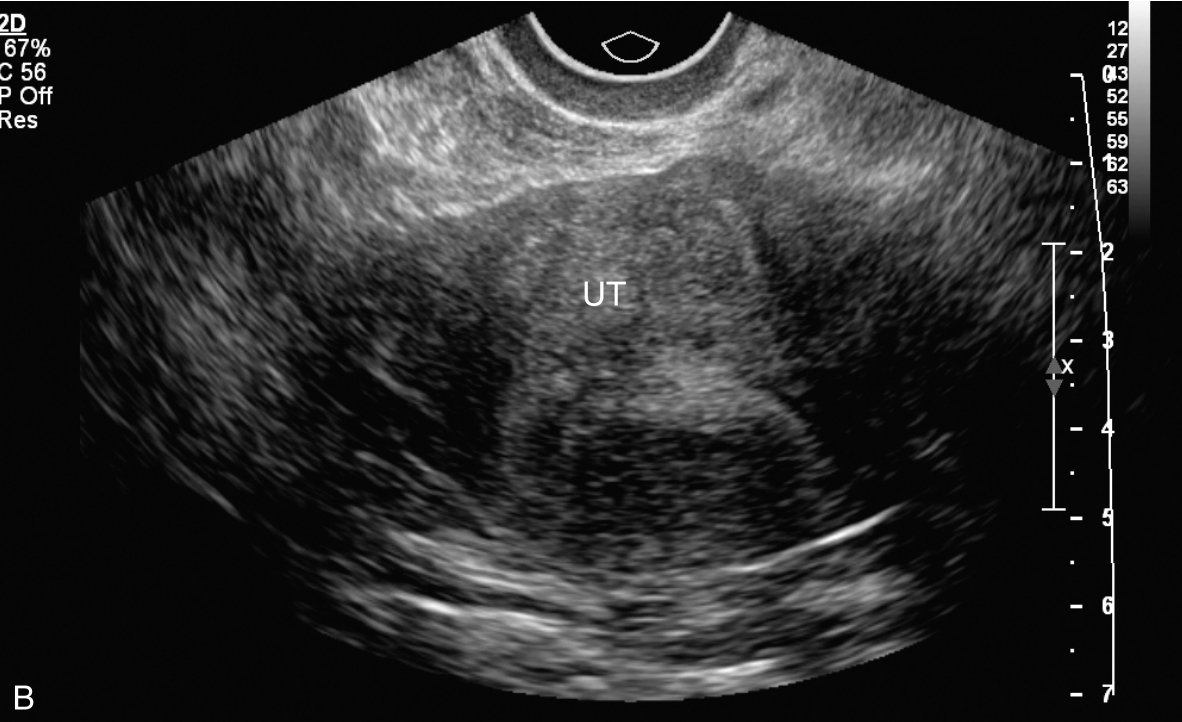

子宫经静脉超声造影见图3-12-3及ER 3-12-1。注入造影剂后16s,子宫内膜开始出现增强(图3-12-3A箭头所示),晚于子宫肌层增强;注入造影剂后23s,子宫内膜呈等增强,造影剂分布不均匀(图3-12-3B箭头所示),其周边出现造影低增强区;注入造影剂后42s,子宫肌层未见异常造影剂聚集(图3-12-3C箭头所示),子宫内膜消退与子宫肌层同步。

图3-12-3 子宫经静脉超声造影声像图

A.注入造影剂后16s;B.注入造影剂后23s;C.注入造影剂后42s。UT:子宫;EN:内膜。